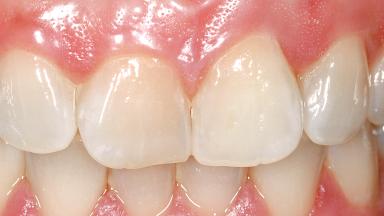

A 29-year-old female patient presented for treatment to replace the upper left central incisor tooth with an implant- supported restoration. The tooth had been intermittently symptomatic for the previous 12 months. The tooth had originally suffered trauma about 15 years previously. Several endodontic treatments had been performed, including an apicectomy procedure to retain the tooth. The patient was healthy and a non-smoker. She had reasonable expectations in regard to esthetic outcomes and the risk of marginal tissue recession following treatment. At medium smile, the gingival margins of the upper teeth were visible, with a display of 3 to 4 mm of the gingival margins. Gingival recession of tooth 21 and a discrepancy in the gingival levels between teeth 11 and 21 was observable during normal speech and smile.

Lip Line No exposure of papillae Exposure of papillae Full exposure of mucosa margin

Periodontal Phenotype Low-scalloped, thick Medium-scalloped, medium-thick High-scalloped, thin